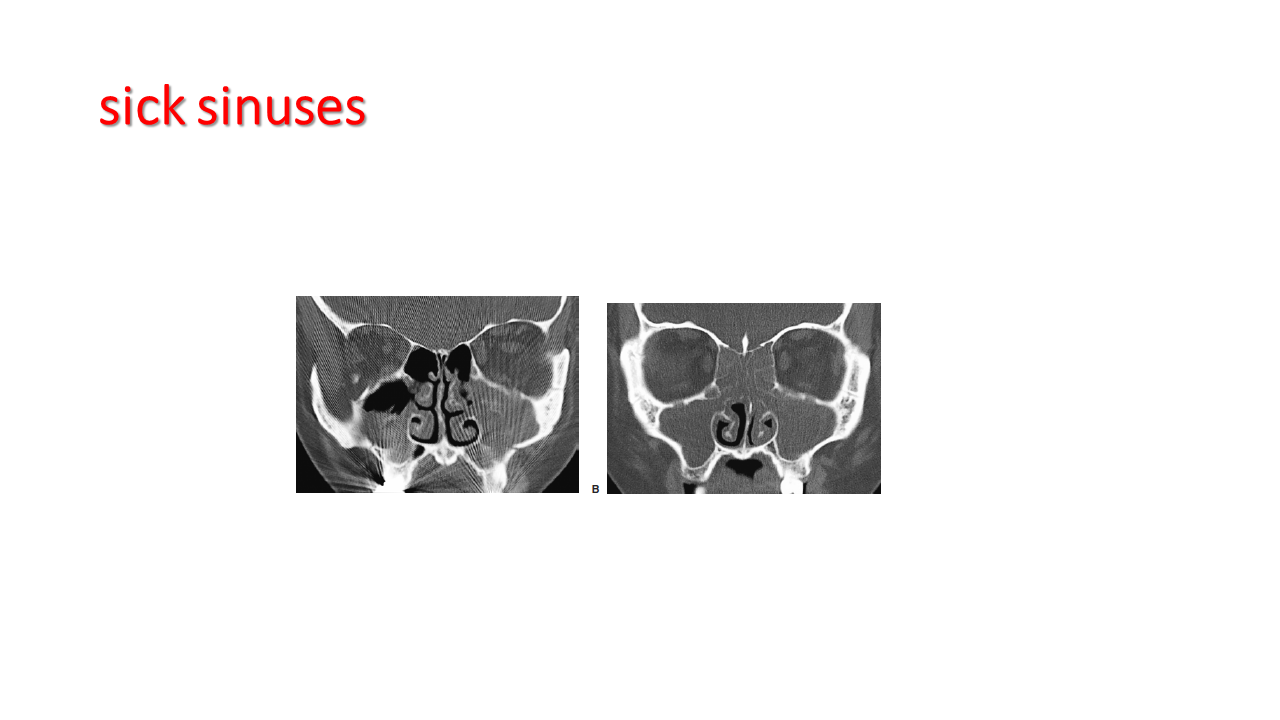

FESS Case Review and Radiologic Analysis (30.09.2016)

Case-based presentation focused on pre- and postoperative imaging in functional endoscopic sinus surgery (FESS). Includes anatomical landmarks, surgical variations, sinus pathology, and technique evaluation. Delivered by Dr. Levon Galstyan at AAOMFS.